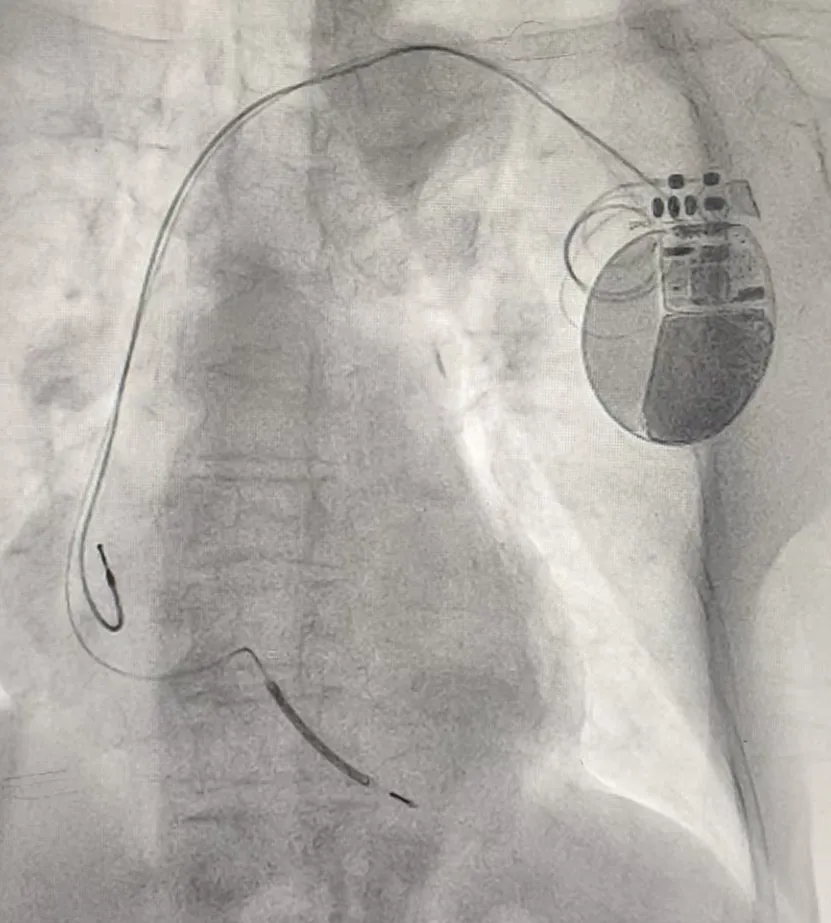

近日,滨州市中心医院入住一名年余90岁的晕厥老人,心血管内科一病区孙桂芳主任团队详细检查评估后,诊断为“室性心动过速”。结合患者身体状况,经充分讨论后,为其植入ICD治疗。

手术过程顺利,术后ICD功能监测各项指标正常,患者未再发作晕厥,现已康复出院,ICD给这位老人带来“心生”。该例ICD植入患者为医院首例,在全市范围内如此高龄患者成功植入ICD也较为罕见。

什么是ICD? ICD是一种植入体内的小型电子医疗设备,植入在胸部皮下,电极导线连接到心脏,主要用于监测心脏节律,并检测到威胁生命的恶性心律失常(如室颤、室性心动过速等)时,通过起搏或电击的方式恢复正常心律,从而预防心脏性猝死。 ICD有哪些功能? 1.心脏电信号监测:ICD能够24小时不间断地监测心脏的电信号,一旦发现恶性心律失常,就会立即启动应对措施。 2.抗心动过速起搏:当ICD检测到心脏出现室速或室颤时,它首先通过快速起搏终止患者的心律失常,这是ICD的无痛性治疗。 3.自动除颤:当抗心动过速起搏仍无法纠正恶性心律失常时,ICD在几秒钟内释放电击终止心脏的异常电信号,使心律恢复正常节律,从而最大限度地减少心脏性猝死的发生。这种电击能量不到体外除颤器除颤能量的十分之一。 4.起搏功能:除了除颤功能,先进的ICD还涵盖普通起搏器的所有功能,如抗心动过缓起搏等。 哪些人需要ICD? 有冠心病、心肌病、心力衰竭、心律失常等心脏病史者;心脏骤停史幸存者;家庭成员有过心脏骤停史者;低射血分数人群(低于35%)。